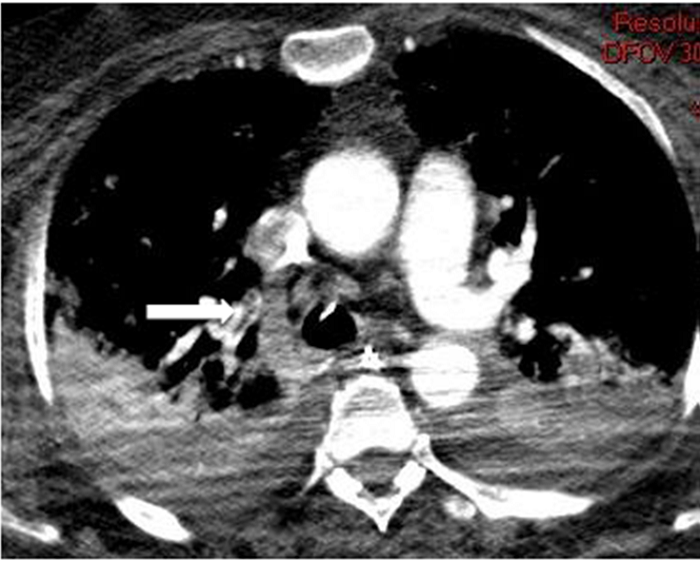

Todos los pacientes de la serie tenían hipoxia y aumento de las cifras de Dímero D con normalización en la cifra de otros parámetros típicamente alterados en esta enfermedad. De los ocho pacientes con TEP solo en dos había afectación múltiple y en ramas principales y lobares (Figura 1). En uno de los dos casos días después se confirmó la existencia de una extensa trombosis de las venas iliacas y femoral derecha como causa del TEP (Figura 2). En los otros seis casos el trombo era único y en ramas de pequeño calibre (Figura 3). En uno de los pacientes el trombo afectaba a la vena pulmonar superior izqda (Figura 4).